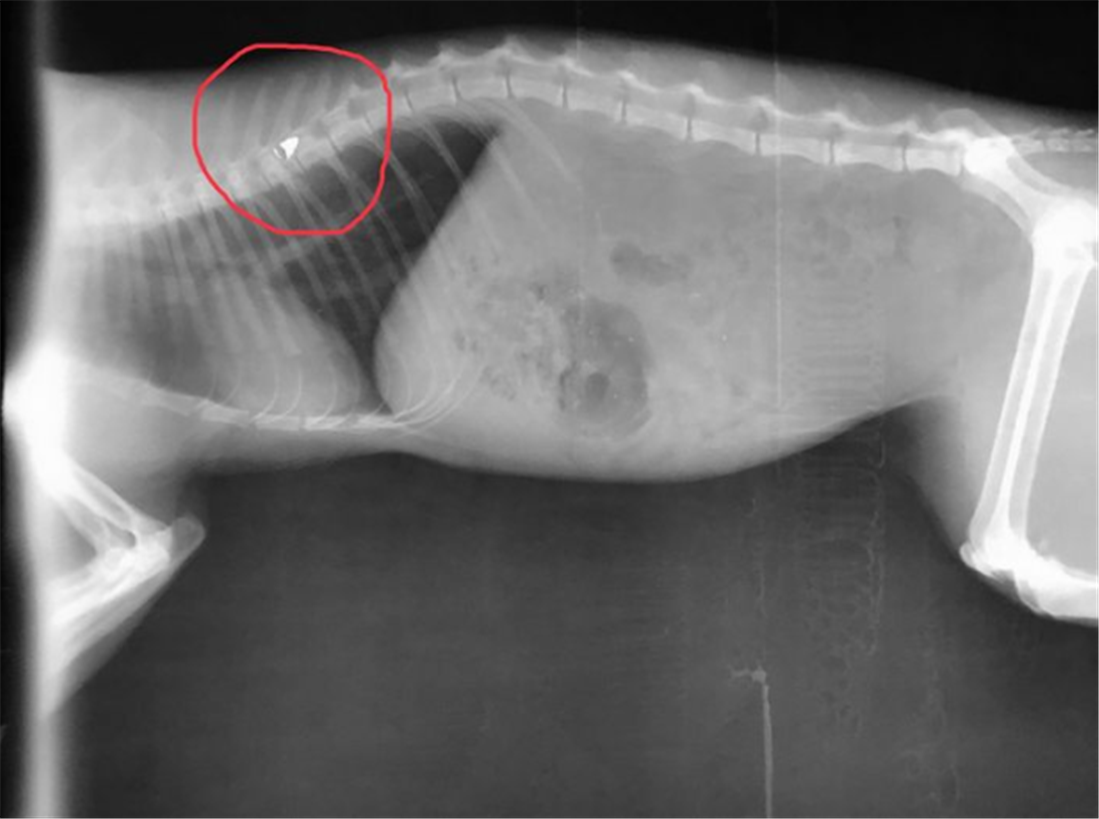

Λυκειάρχης σε σχολείο της Λαμίας πυροβόλησε το άτυχο ζώο με αεροβόλο, με τη βολίδα να σφηνώνεται στη σπονδυλική του στήλη και να μένει παράλυτο...

Η υπόθεση έφτασε το πρωί της Παρασκευής 12 Ιουλίου στο Αυτόφωρο Μονομελές με κατηγορούμενο έναν Λυκειάρχη, ο οποίος φέρεται να πυροβόλησε το άτυχο ζώο με αεροβόλο, με τη βολίδα να σφηνώνεται στη σπονδυλική του στήλη και να μένει παράλυτο.